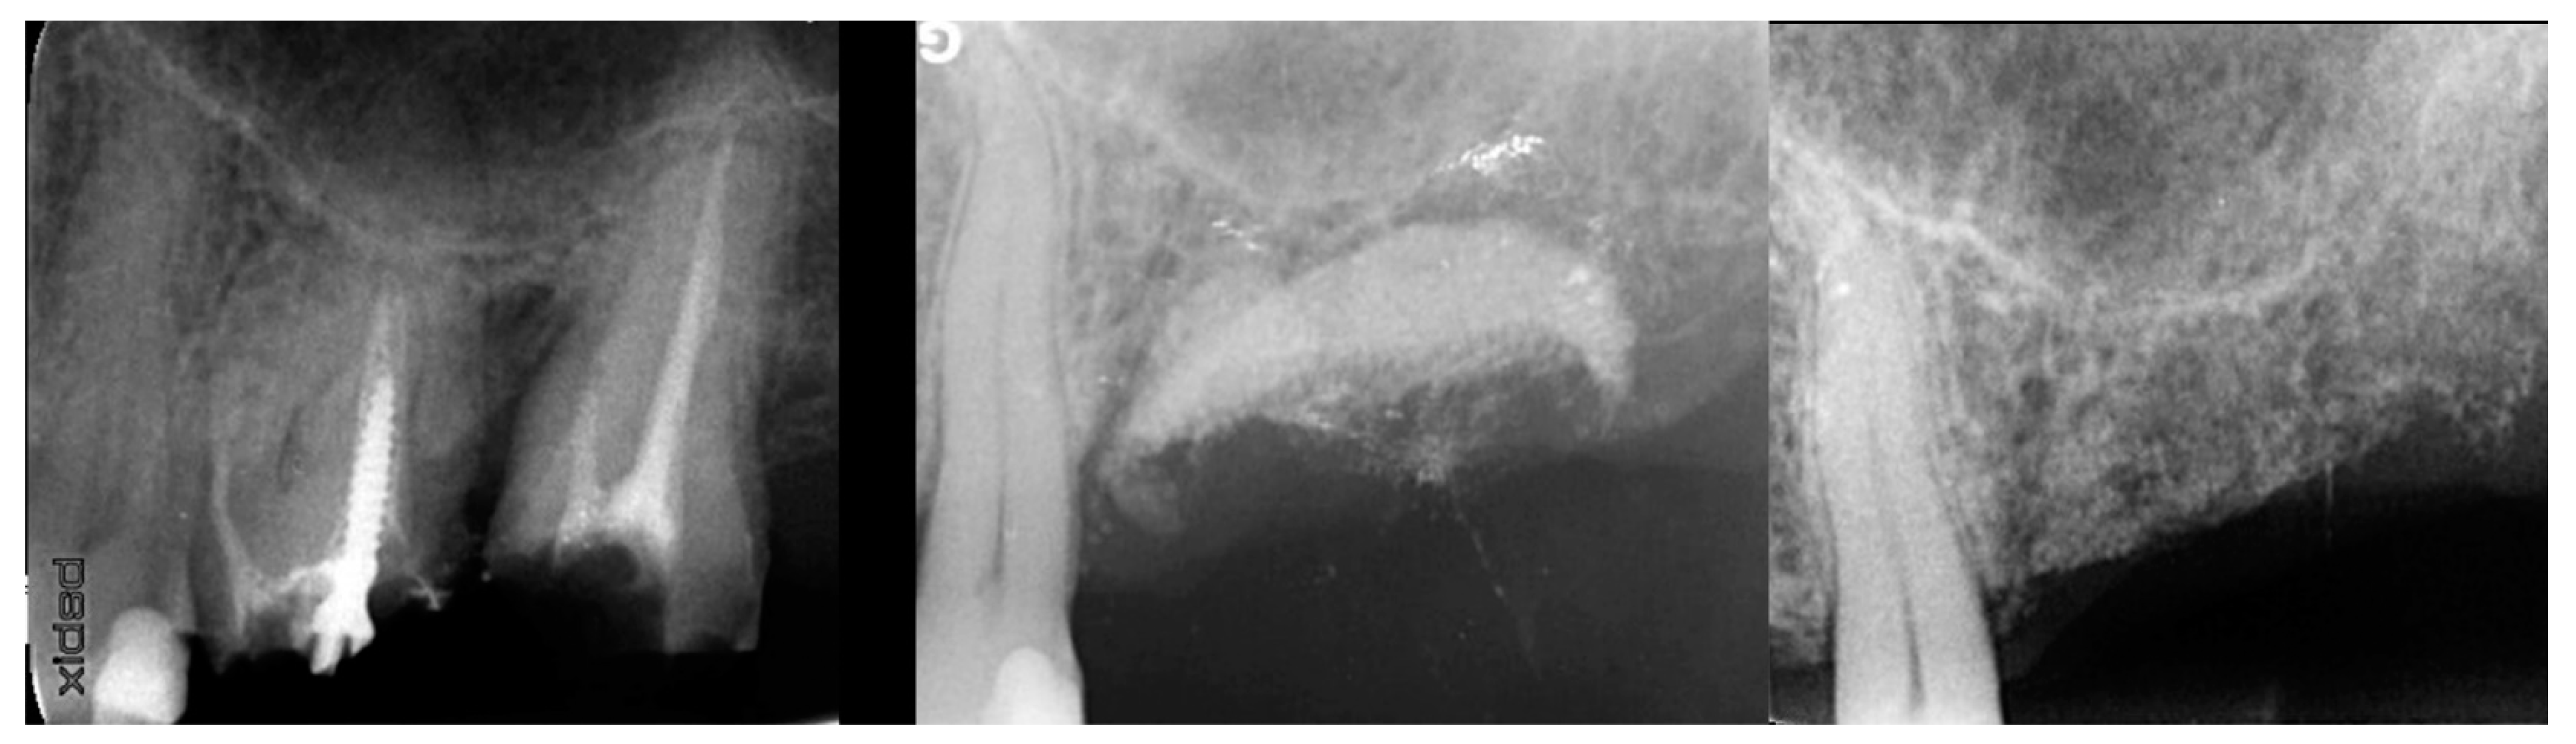

Figure 8.

Failing 1st and 2nd molars related to periodontal bone loss (left), the site following 10 weeks of healing to allow soft tissue closure over the ridge (middle) and a radiograph demonstrating the available bone between the crest and sinus for implant placement (right).

At 10 weeks post-extraction, the patient presented, and consent forms were reviewed and signed for grafting and implant treatment. Soft tissue had healed, closing the site with keratinized tissue (Figure 8, middle). A radiograph was obtained to check what available bone was present at both sites (Figure 8, right). Sufficient height was available to place an implant at the 1st molar site in conjunction with a crestal sinus augmentation, but insufficient height was present at the 2nd molar site which would require grafting to increase crestal height and later implant placement could be performed at that site.